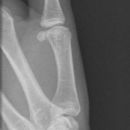

Bennett Fraktur